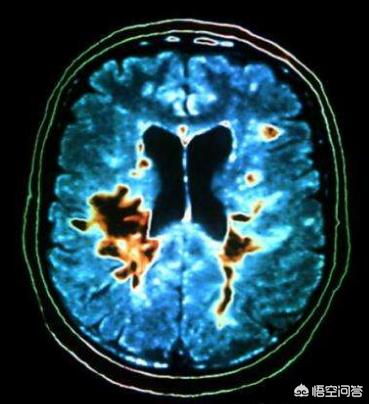

L'infarctus cérébral est très fréquent en dehors du système cérébro-vasculaire, il est le tueur implacable des personnes d'âge moyen et des personnes âgées ! Son danger réside dans le taux élevé d'invalidité qui s'ajoute à la mort ! Il survient rapidement et se développe encore plus vite ! Afin de vous donner une idée visuelle de la situation, veuillez consulter la figure suivante.

👆👆👆 这是脑梗死的缺血半暗带,脑组织缺血1分钟组织就开始缺血缺氧,脑细胞开始发生变化。30分钟就能看到明显的梗死灶,随后梗死灶逐渐扩大!3个小时候和刚开始对比,梗死范围已经非常大了! Par conséquent, les patients atteints d'infarctus cérébral sont dans une course contre la montre, courir vite avec un taux de survie élevé et un taux d'invalidité faible, courir lentement avec un taux de survie faible et un taux d'invalidité élevé !